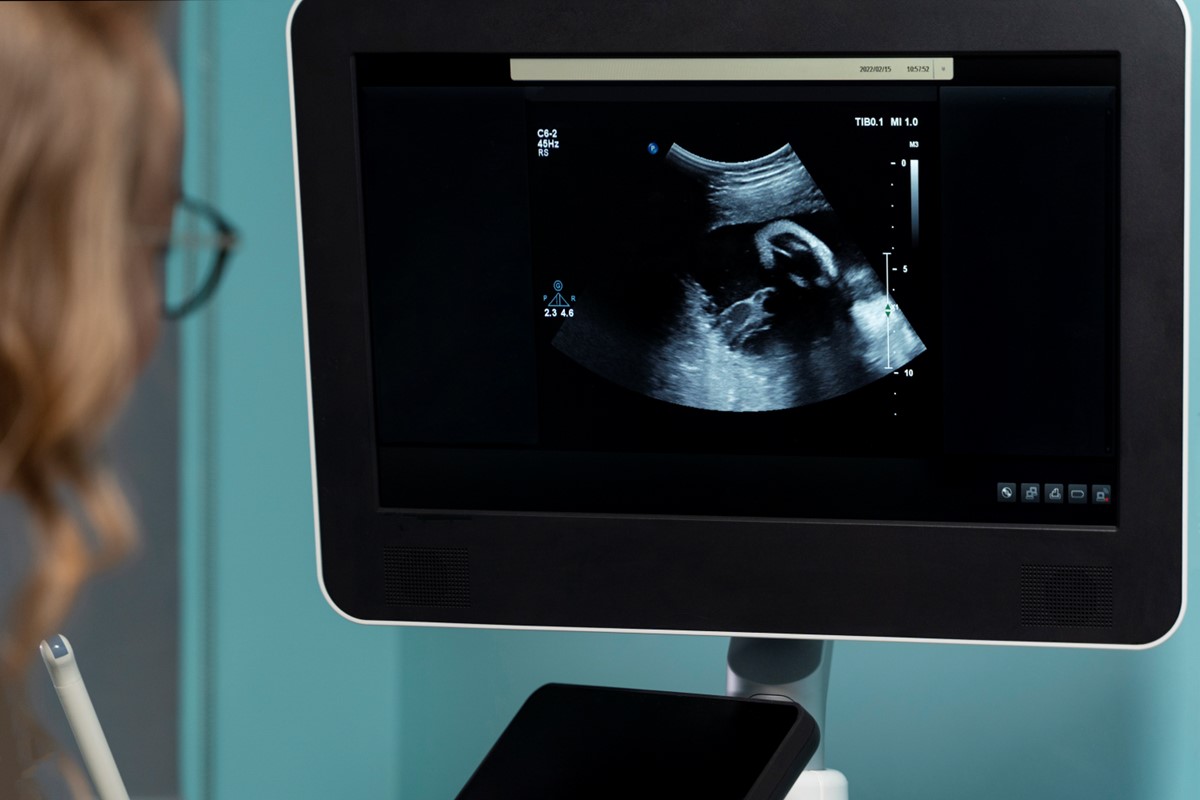

The Importance of Ultrasonography in Obstetrics: A Guide for Expecting Parents

What is Ultrasonography in Obstetrics? Ultrasonography in obstetrics is a safe imaging test used during pregnancy. It uses sound waves to create pictures of the

Growth Scan in Pregnancy: What to Expect, Benefits, and Key Insights

Introduction During pregnancy, regular check-ups help keep both mother and baby healthy. One important test is the growth scan in pregnancy. This scan checks how

3D Ultrasound: What It Is, How It Works, and What to Expect

Introduction 3D ultrasound is a special type of medical scan. It uses sound waves to create three-dimensional images of the inside of the body. Because

What is 3D Scan in Pregnancy?

A 3D scan in pregnancy is a medical imaging technique that uses ultrasound technology to create a 3D image of a developing fetus. This type